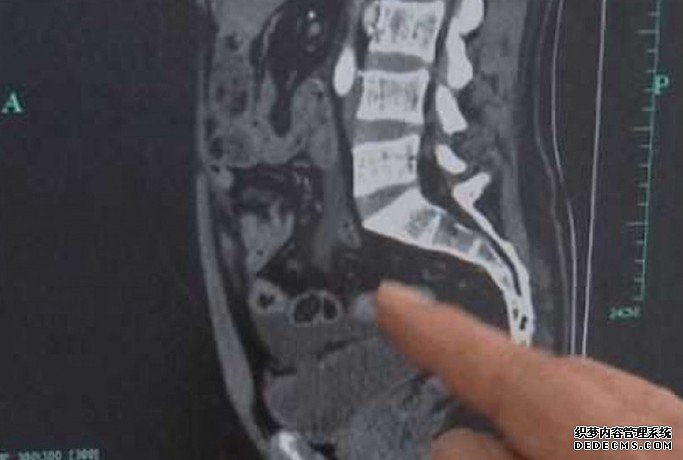

后来到当地绍兴医院求医,医生惊讶发现胡男的膀胱竟有3个裂洞。其中一个洞更因为太接近胡男腹部,导致部分肠子掉进膀胱中,医师尝试让胡男自行排尿却失败。胡男表示,从喝酒开始都没有排尿,回家睡了18小时也都没排尿。

医生立刻决定替胡男进行手术,沐鸣直属代理修补膀胱上的洞。院方表示「人类的膀胱是相当有弹性的,可以随著尿液增大或是缩小,容量大约350到500毫升,喝过酒的人可能因为神经系统受到酒精抑制,所以不太会有想上厕所的感受。」儘管这样的病例很罕见,但1年中仍会有1到2位这样的患者。